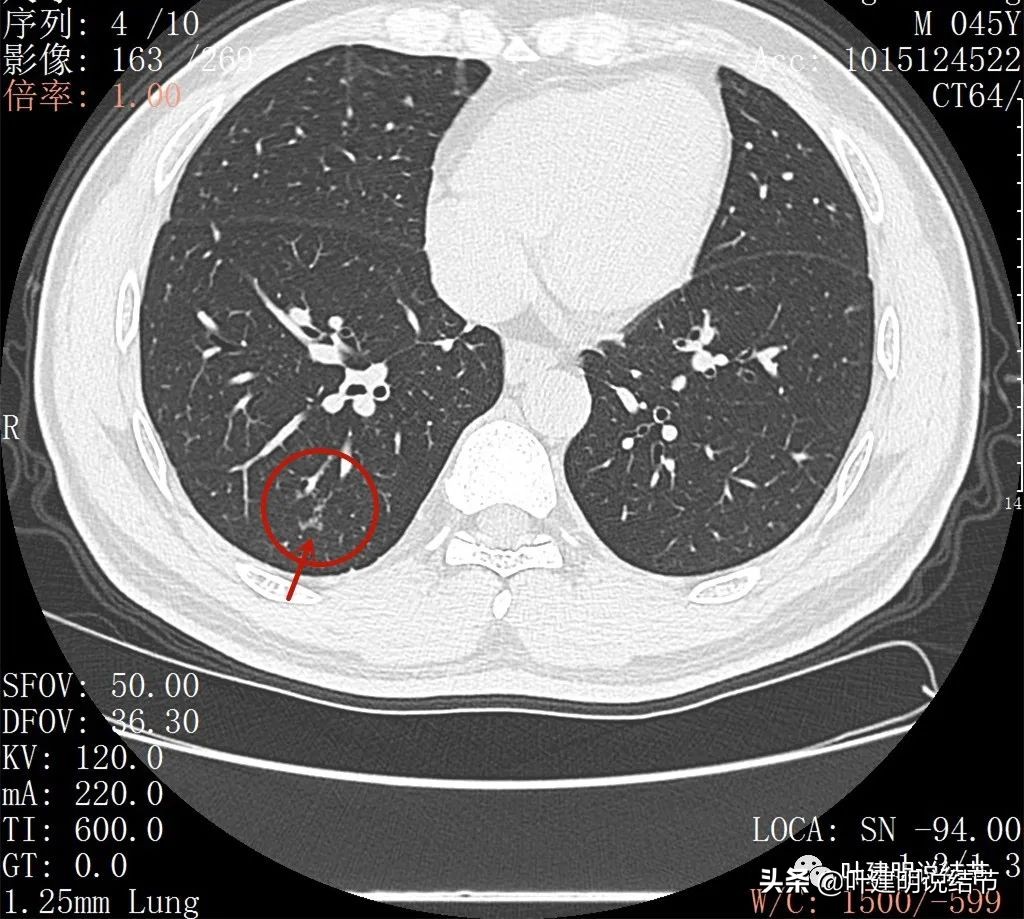

2022年5月复查靶扫描的图像:

病灶出现,磨玻璃密度,非圆形或类圆形,感觉比较散

病灶虽然不密,但轮廓较清,磨玻璃成分明显,感觉偏向恶性

病灶有少许实性成分(粉色箭头)

病灶似有血管进入(桔色箭头),而且血管异常增粗,整体病灶轮廓较清,似有分叶,中间有空泡征呈蜂窝状

病灶内部见血管穿行,轮廓与瘤肺边界清楚

扩张的细支气管感觉较为僵硬

少许区域有密度较高的部分,扩张细支气管明显,且显僵硬

病灶较散在

病灶形态不规则,不是圆形或类圆形

此层见病灶边缘显糊

病灶显模糊,感觉过于散在了些

病灶形散,密度低